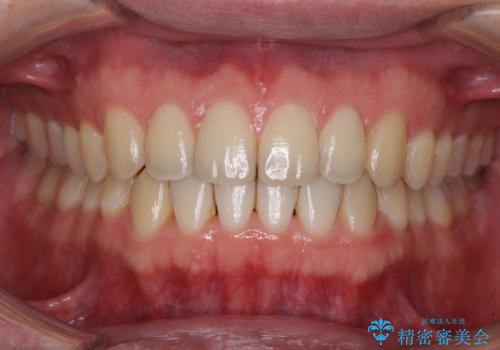

【モニター】インビザラインで口を閉じやすく

- 前に出ている上顎前歯が気になるとのことで来院された患者様です。

インビザラインを用い、IPR(歯と歯の間を削る)と歯列全体を後方に移動させることで、可能な限り前歯の突出感を改善することとしました。

元々の歯列も整っており、横顔の印象の出っ歯ではなかったため、仕上がりに満足できない可能性があると心配しておりましたが、口が閉じやすくなり、患者様には大変満足していただきました。